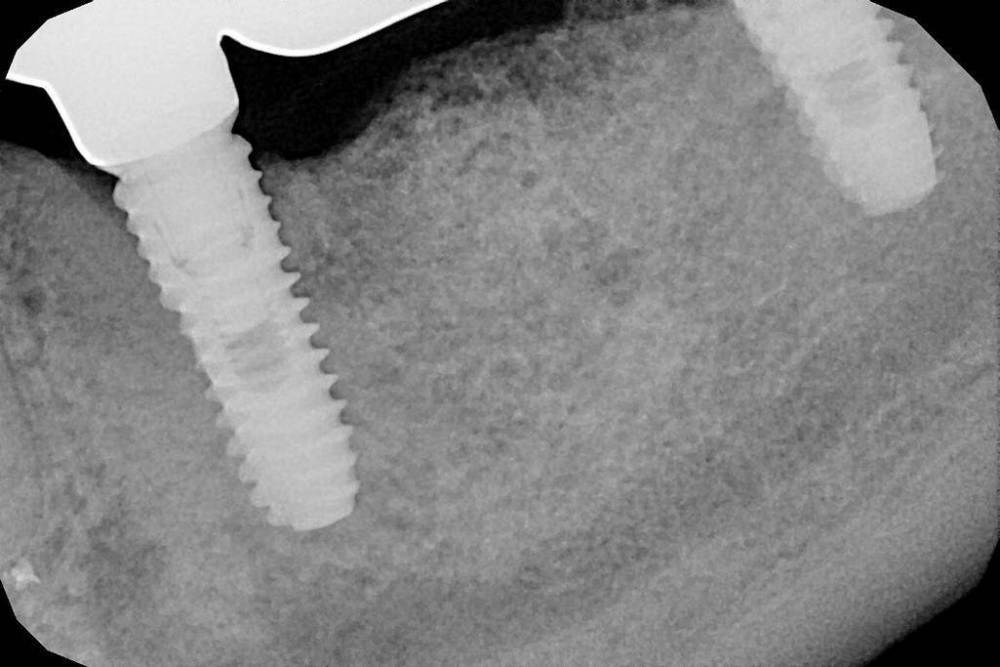

Tarissa Опубликовано 3 марта, 2023 Поделиться Опубликовано 3 марта, 2023 (изменено) Здравствуйте! Примерно 5 лет назад была проведена имплантация и протезирование. В течение месяца после протезирования, имплантаты «на пару витков» оголились. Но врач успокоил меня, сказав что «так должно быть». Неделю назад, в области имплантатов, при надавливании, из десен 5 и 7 стал появляться гной, а в 5-м и кровь. Болевых ощущений нет., десны не красные. Вчера я снова обратилась к своему доктору. Сделала КТ , (если нужно, постараюсь здесь выложить). Мост он снял. Также, было произведено тестирование имплантатов прибором на предмет остеоинтеграции, результат 82 и 85.( Не знаю, насколько это полезная информация)… После снятия протеза почувствовала во рту оч. неприятный гнилостный запах и вкус крови. Доктор подавил инструментом вокруг имплантов, (было больно), промыл лунки имплантов и установил мост обратно. Мне было сказано, что «ничего страшного нет, есть воспаление и нужно некоторое время пополоскать рот антисептиками». Сегодня я сделала панорамный снимок и, как мне кажется, ситуация с костью вокруг имплантатов ухудшилась по – сравнению с 2018 годом. Сейчас, при надавливании гной тоже есть, но в меньшем количестве. Прошу, посмотрите пожалуйста снимки. Это переимплантит? Лечить его или удалять все и делать заново? 1-й снимок - До протезирования, январь 2018. 2 и 4-й снимок. Через месяц после установки моста , июль 2018г. 3-й снимок. март 2023 Изменено 3 марта, 2023 пользователем Tarissa редактирование Ссылка на комментарий